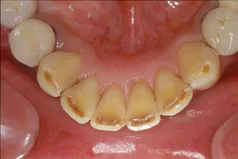

[症例1]

歯石除去だけでは取りきれないタバコのヤニなどのステインもエアーフローという機械を用いて除去しています。

• 治療期間:1ヶ月

• 治療費:保険適応内治療

• 治療回数:3回